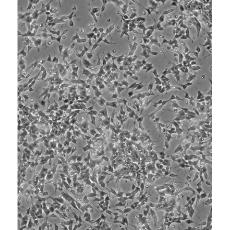

SH-SY5Y [SHSY-5Y]

產(chǎn)品名稱 SH-SY5Y [SHSY-5Y]

中文名稱 人神經(jīng)母細(xì)胞瘤細(xì)胞

組織來源 神經(jīng)母細(xì)胞瘤;骨髓來源;男性

細(xì)胞種屬 Homo sapiens, human

生長(zhǎng)特性 mixed, adherent and suspension

形態(tài)特征 epithelial-like and neuronal-like

細(xì)胞描述 SH-SY5Y cells have a reported saturation density greater than 1×10^6 cells/cm^2. They are reported to exhibit moderate levels of dopamine beta hydroxylase activity. Ref